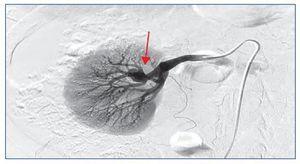

Mediante microcateterismo superselectivo de la rama eferente, se cateteriza el aneurisma y se emboliza mediante coils GDC de liberación controlada (figuras 3 y 4).

Figura 4. Embolización mediante coils GDC de liberación controlada.

La angiografía de comprobación muestra una correcta oclusión del aneurisma.